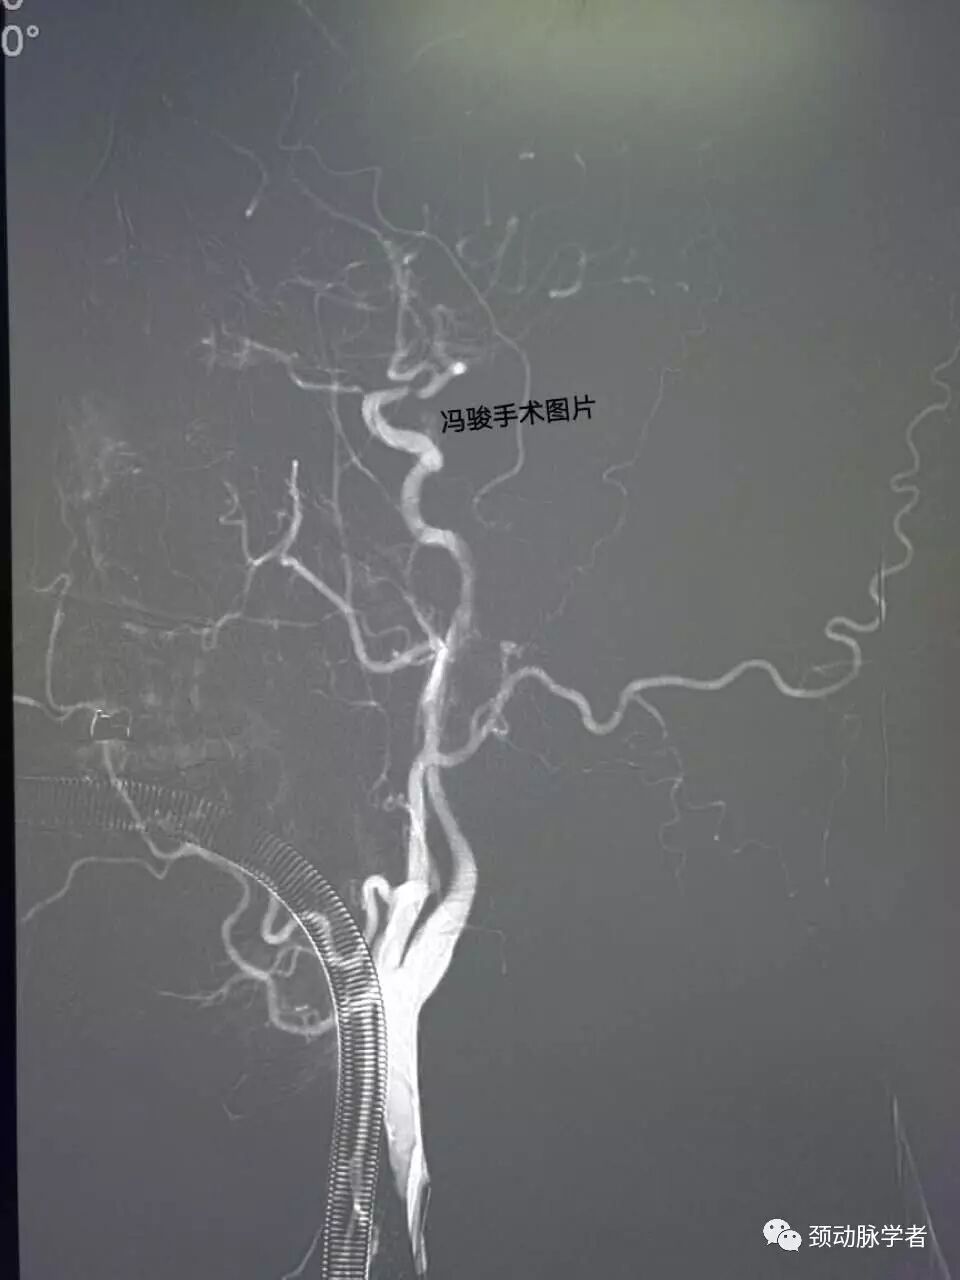

精准定位后,释放2.5-8mm,apollo支架,再次造影显示,狭窄解除,血流通畅。

术后患者复苏,血压稳定,无特殊不适,症状再无发作,家属非常激动,送来锦旗感谢,满意出院。